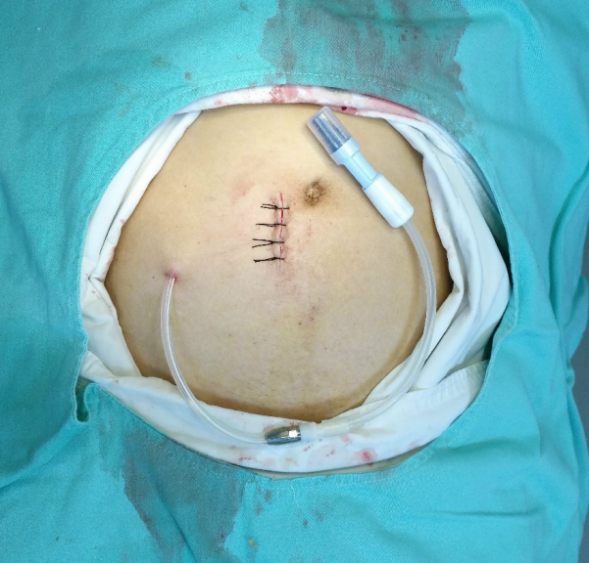

3.B超引导下肾穿刺活检术、腹透管植入术以及经皮内瘘血管形成术(PTA)、动静脉内瘘成形术以及透析血管通路的并发症诊治;

肾穿刺活检术

图 腹膜透析置管